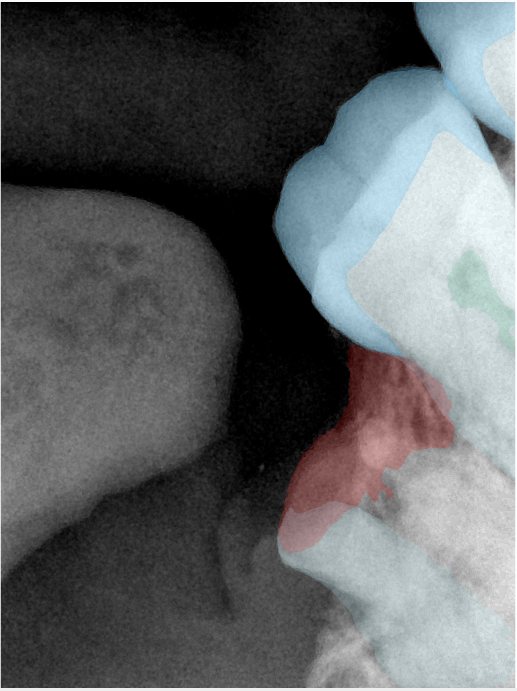

CR/DR 牙齿分割阶段记录

当前进展

- 完成了 CR/DR 牙齿相关分割训练

- 当前结果已经达到阶段预期,但仍有细节问题需要继续处理

相关测试

遇到的问题

- 训练过程中出现过 mask 下移问题

- 部分结果会出现 box 填充异常

- mask 边缘仍然有比较明显的锯齿感

参考

第二版算法问题测试

Updated: 2026-04-13(更新日期)

| 第一版 | 第二版 | 是否解决 | |

|---|---|---|---|

![]() | ![]() ![]() 边角识别有问题 龋齿识别不全 牙髓识别不全 | ![]() | 解决 |

![]() | ![]() 边角识别有问题 识别信息有误 自查(牙冠识别不全) | ![]() | 解决 |

![]() | ![]() ![]() 边角识别有误 大范围填充识别遗漏 | ![]() | 解决 |

![]() | ![]() 识别信息不全 | ![]() | 解决 |

![]() | ![]() ![]() 边角问题 牙胶识别不全 牙冠识别不全 | ![]() | 解决 |

![]() 换图片 | ![]() | ![]() 牙冠部分稍微白了一些就识别成小范围修补,部分判断异常 | 部分解决,修复类略敏感,牙冠部分稍微白了一些就识别成小范围修补,部分判断异常。 |

![]() | ![]() ![]() 牙冠识别不全 牙髓不全 根尖炎龋齿识别有误 | ![]() | 解决 |

![]() | ![]() | ![]() | 解决 |

![]() 换图片 | ![]() | ![]() | 解决 |

![]() | ![]() 牙冠识别有误 | ![]() | 解决 |

![]() 换图片 | ![]() ![]() 边角识别有误 | ![]() 修复类敏感 | 部分解决,图像过白,导致修复类判断异常。 |

![]() 换图片 | ![]() 牙冠识别不全 | ![]() 修复类敏感 | 部分解决,图像过白,导致修复类判断异常 |

结论:修复类出现了不鲁棒的情况,后续需要加入轮廓的扩充数据进行增强。